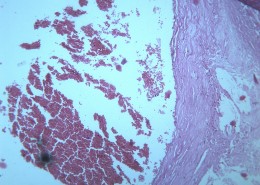

首页 > 其他类别 > 动脉粥样硬化(12张) > 动脉粥样硬化 第1张

动脉粥样硬化 - 第1张

猫扑风铃上传动脉粥样硬化 图集中 / 共有 12 张图片